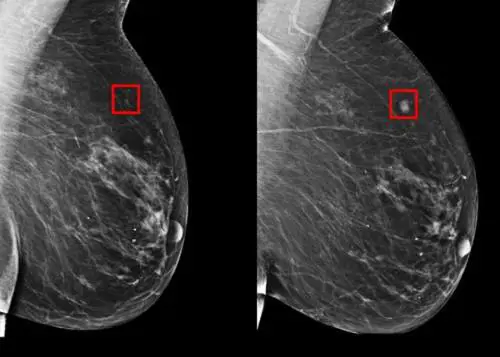

cancro al seno

Alcuni cambiamenti che interessano il seno possono suggerire la presenza di un tumore alla mammella. Non è sempre vero, ma in alcuni casi è saggio e prudente consultare un medico. Dolore, noduli, piaghe,quando dovresti preoccuparti per il tuo seno? Ci sono segnali a cui prestare attenzione.

Quali sono i sintomi del cancro al seno a cui prestare attenzione